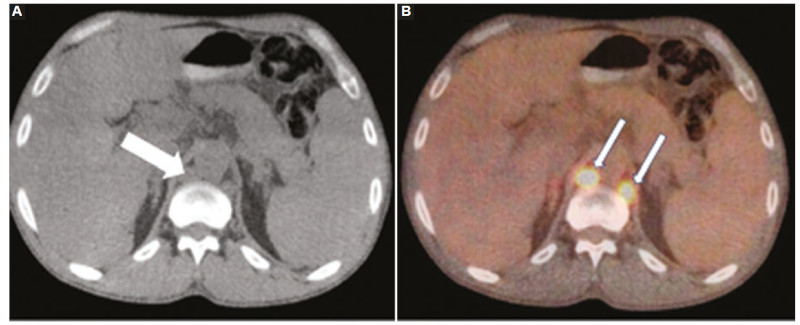

Las adenopatías asociadas al SLPT suelen verse como ganglios aumentados de tamaño, con escaso realce con el contraste endovenoso, homogéneos y con pérdida de su hilio graso en la mayoría de los casos28. Si bien puede afectarse cualquier sitio nodal, los lugares comprometidos más frecuentes son el mediastino y el retroperitoneo, en general acompañando un compromiso extraganglionar a nivel del tórax o cavidad abdominal, respectivamente.

Los estudios de PET-TC mostrarán aumento del consumo de FDG de las adenopatías (Fig. 3), con un SUV promedio entre 8 y 17 según algunos autores29,30.

La PET-CT puede mostrar casos de falsos positivos en infecciones y procesos inflamatorios, o bien falsos negativos debido a lesiones de pequeño tamaño, reportándose una sensibilidad aproximada al 89% para el diagnóstico del SLPT30. La PET-CT es útil para realizar diagnósticos diferenciales de esta entidad, así como para colaborar en una evaluación más precisa de la extensión y estadio de la enfermedad31.